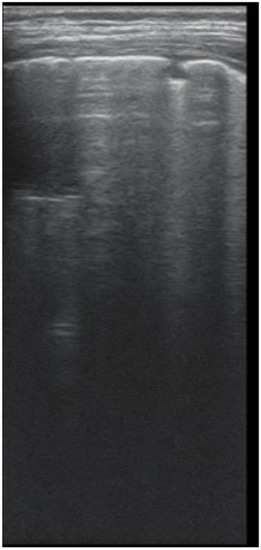

As for varicose bronchiectasis (Figure 9 A,B), a very low Sp = 25% and NPV = 16.6% were calculated, with a satisfactory PPV = 88.8% and Se = 68.4%.

Figure 9. (A) LUS: coalescent B lines, loss of A lines. (B) CT image: (1) cylindrical bronchiectasis with moderate wall thickening; (2) varicose bronchiectasis; (3) saccular bronchiectasis with moderate wall thickening; and (4) several bronchiectasis with mucus plugging.